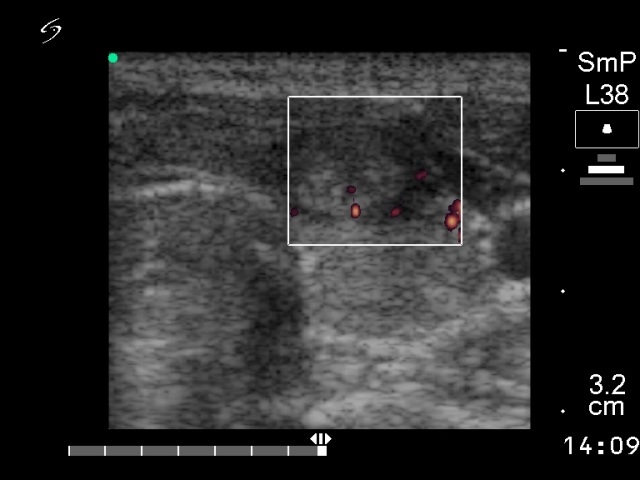

Ultrasonography: the thyroid was echonormal with small hypoechogenic foci. An echonormal nodule with a halo sign in the left lobe.

Second, the presence of small hypoechogenic foci on ultrasonography, the high-normal level of the TSH, and the oxyphilic metaplasia all independently raised the possibility that this patient had a lymphocytic thyroiditis. It seems logical, that anti-TPO determination were of help. We performed that and it resulted in a normal level (below 10 IU/mL). The problem was that in initial phase of a Hashimoto's thyroiditis, anti-TPO is rarely positive. Moreover, an elevated anti-TPO level is a proof for an autoimmune disorder, but does not exclude the possibility of malignancy.